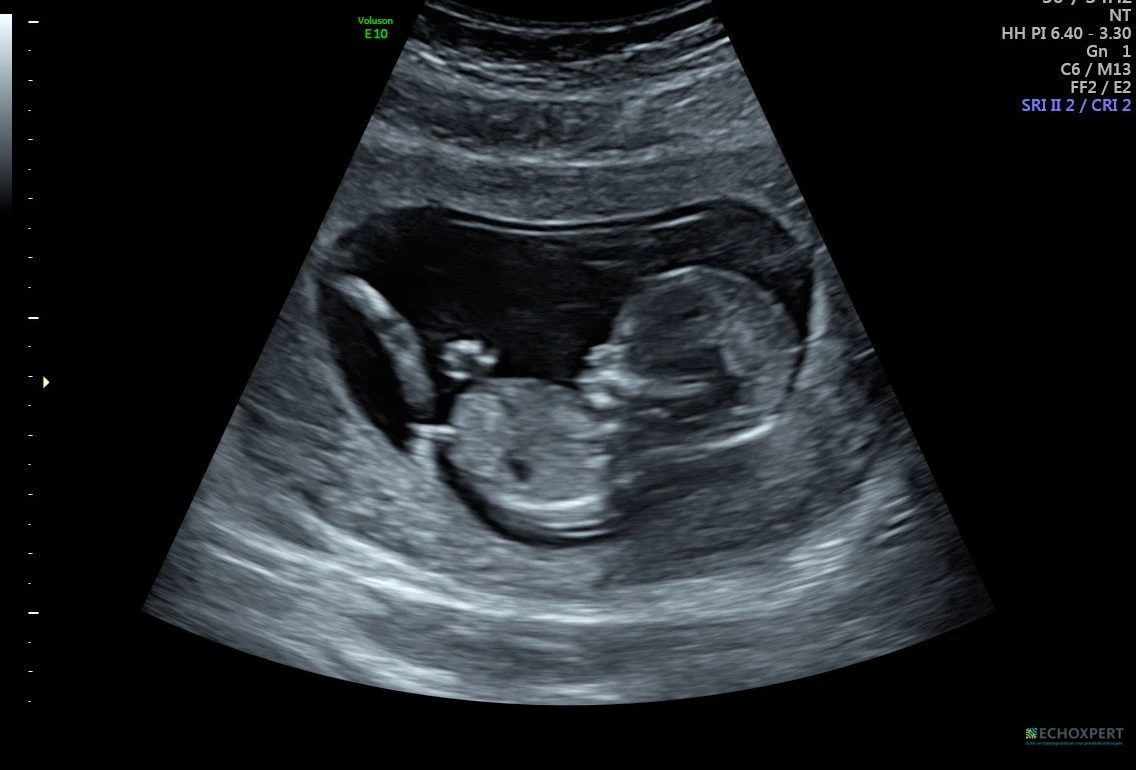

프로젝트 화면으로 아기의 옆모습이 보였다. 어디가 코인지, 턱인지 제법 구분도 잘 되는 데다 몸속에서 빠른 속도로 뛰는 심장도 선명하게 볼 수 있었다. 아, 좋은 초음파 기계라는 게 이런 거였구나. 그전까지 언제나 조금씩 흐릿하게 보여서 온갖 상상력과 공간지각력을 동원했어야 했던 지난 초음파 검진들이 순식간에 지나갔다.

“목 투명대도 2.3mm로 정상이고, 머리-엉덩이 길이도 7.2cm니까 아주 잘 자라고 있네요.”

그리고 초음파 선생님은 이곳저곳을 비춰가면서 심장이 잘 뛰고 있는지, 팔다리, 손발은 다 잘 발달하고 있는지, 뇌는 예쁘게 만들어지고 있는지, 탯줄과 태반은 잘 자리를 잡았는지 등을 약 20분간 꼼꼼하게 검사했다.

“보세요, 아기가 손을 흔드네요. 기지개도 켜고요.”

그리고 조금 남은 시간 동안 초음파로 아이의 모습을 이리저리 볼 수 있었다.

나의 최애 순간. 아주 능숙하게 다리를 꼬는데 이거 이거…